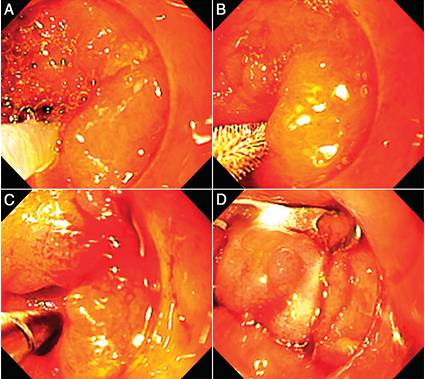

哎呀,说到克罗恩病,这可不是个让人轻松的话题啊!这病啊,就像个顽皮的小鬼,总是悄无声息地侵入我们的生活,让人的肚子疼得死去活来。西医的治疗方法虽然科学,但有时候总觉得少了点什么,让人心里空落落的。

直到有一天,我听说了中西医结合疗法,心里那叫一个激动啊!中医的那一套,什么针灸、草药,听起来就让人觉得神秘又充满希望。想着那些细细的针扎进皮肤,说不定就能把那捣蛋的小鬼赶走,心里就有点小激动呢!

而且啊,听说中西医结合不仅能缓解症状,还能调整身体的整体状态,这不就是传说中的“治标又治本”吗?每次去医院,看到那些医生认真地给我把脉、开方子,心里就觉得特别踏实。虽然治疗过程有时候会有点小痛苦,但想到未来可能不再被疼痛困扰,就觉得一切都值了。

这种疗法,就像是给克罗恩病患者打开了一扇新的大门,让我们看到了不一样的希望。